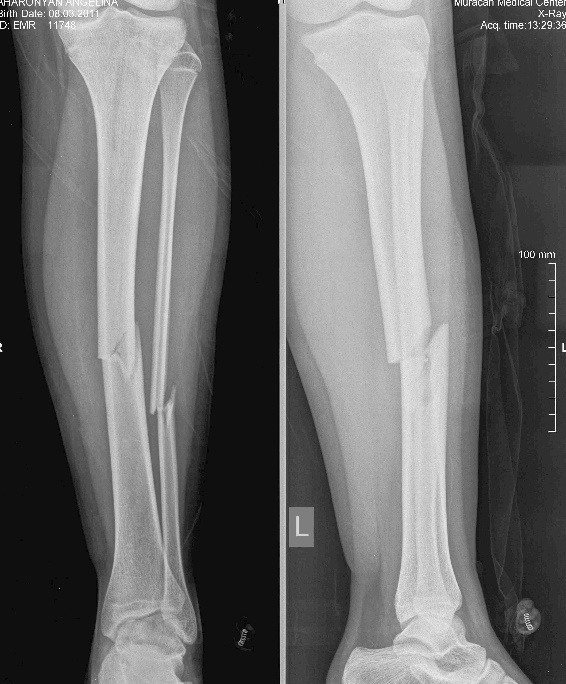

Այս ուսումնասիրությունը հիմնված է 21 հիվանդների (17 տղա, 4 աղջիկ) շարունակական խմբի բուժման արդյունքների վերլուծության վրա, որոնք ենթարկվել են տիտանե էլաստիկ մեխերով վիրահատության։ Հիվանդների տարիքը եղել է 4 տարեկանից մինչև 16 տարեկան։ 9 երեխայի մոտ կոտրվածքի պատճառ է հանդիսացել ձեռքի վրա անկումը, մնացածի մոտ կոտրվածքն առաջացել է վերջույթի ոլորման արդյունքում, վնասվածքի մեխանիզմը եղել է ուղիղ: 19 դեպքերում կոտրվածքները եղել են փակ, իսկ 2 դեպքում՝ բաց։ Ըստ վնասվածքի տեղայնացման՝ դրանք եղել են դիաֆիզար կոտրվածքներ (15 դեպք), պրոքսիմալ մետաֆիզի մակարդակի կոտրվածք (3 դեպք) և հեռավոր մետաֆիզի՝ (3 դեպք): Կոտրվածքային գծի բնույթի համաձայն՝ դիաֆիզային կոտրվածքներից հայտնաբերվել են 6 լայնակի, 4 թեք, 5 պտուտակաձև։ Մի տղայի մոտ (4 տարեկան), որի մոտ առկա էր սրունքի մ/3-ի բաց թեք կոտրվածք տեղաշարժով և մաշկի մինուս հյուսվածքներով, կատարվել է նաև վերքերի առաջնային վիրաբուժական մշակում և կարում՝ ռետինյա արտաթորիչներով։ Սակայն մի քանի շաբաթ անց սկսվել է մաշկի նեկրոզ։ Այդ իսկ կապակցությամբ կատարվել է երկրորդ վիրահատական միջամտությունը։ Կատարվել է մաշկի աուտոտրանսպլանտացիա։ Մաշկի կտորները վերցվել են առողջ ազդրի առաջային մակերեսից: (Նկ 1)

Վնասվածքից հետո առաջին օրվա ընթացքում վիրահատվել է 10 երեխա, 2-3-րդ օրը՝ 8 երեխա, իսկ վնասվածքից ավելի քան 3 օր անց՝ 3 երեխա։ Վիրահատության միջին տևողությունը կազմել է 60 րոպե։ Հոսպիտալացման տևողությունը միջինը կազմել է 3 օր: Ցավային սինդրոմը թեթևացել է վիրահատությունից հետո 3-7-րդ օրը, ինչը հնարավորություն է տվել ակտիվ շարժումներ սկսել հարակից հոդերի վրա՝ առանց լրացուցիչ բեռի:

Երեխաները վիրահատված վերջույթը սկսել են օգտագործել առօրյա կյանքում (սնվել, հագնվել, հիգիենայի պարագաներ օգտագործել) օստեոսինթեզից 10-12 օր հետո։ Դպրոց հաճախելը վերսկսվել է հիվանդանոցից դուրս գրվելուց 7-10 օր հետո: Վիրահատված վերջույթի շարժման տիրույթի ամբողջական վերականգնում նկատվել է բոլոր երեխաների մոտ վիրահատական բուժումից 4-5 շաբաթ անց՝ անկախ կոտրվածքի բնույթից։ Սպորտին վերադարձը տեղի է ունեցել վիրահատությունից հետո 6 շաբաթից մինչև 3 ամիս ընկած ժամանակահատվածում՝ կախված սպորտի տեսակից և կոտրվածքի բնույթից։ Ինտրամեդուլյար մեխերի հեռացումը կատարվել է 15 դեպքերում օստեոսինթեզից 6 և ավելի ամիս անց, իսկ մնացած դեպքերում 12 ամիս անց։ Իմպլանտը հեռացվել է ընդհանուր անզգայացման տակ։ Իմպլանտի հեռացման ընթացքում կամ դրանից հետո բարդություններ չեն եղել: Բուժման ավարտից և իմպլանտների հեռացումից հետո հիվանդների արդյունքները գնահատելիս բոլոր դեպքերում գրանցվել է գերազանց արդյունք։ Հանդիպած բարդություններից եղել է 2 դեպք։ Մեկը՝ մաշկի նեկրոզ, որը պայմանավորված էր մեծ վերքի առկայությամբ կապված վնասվածքի բնույթից (ավտովրաերթ), և երկրորդը՝ ձողով մաշկի պերֆորացիա և թարախակալում։